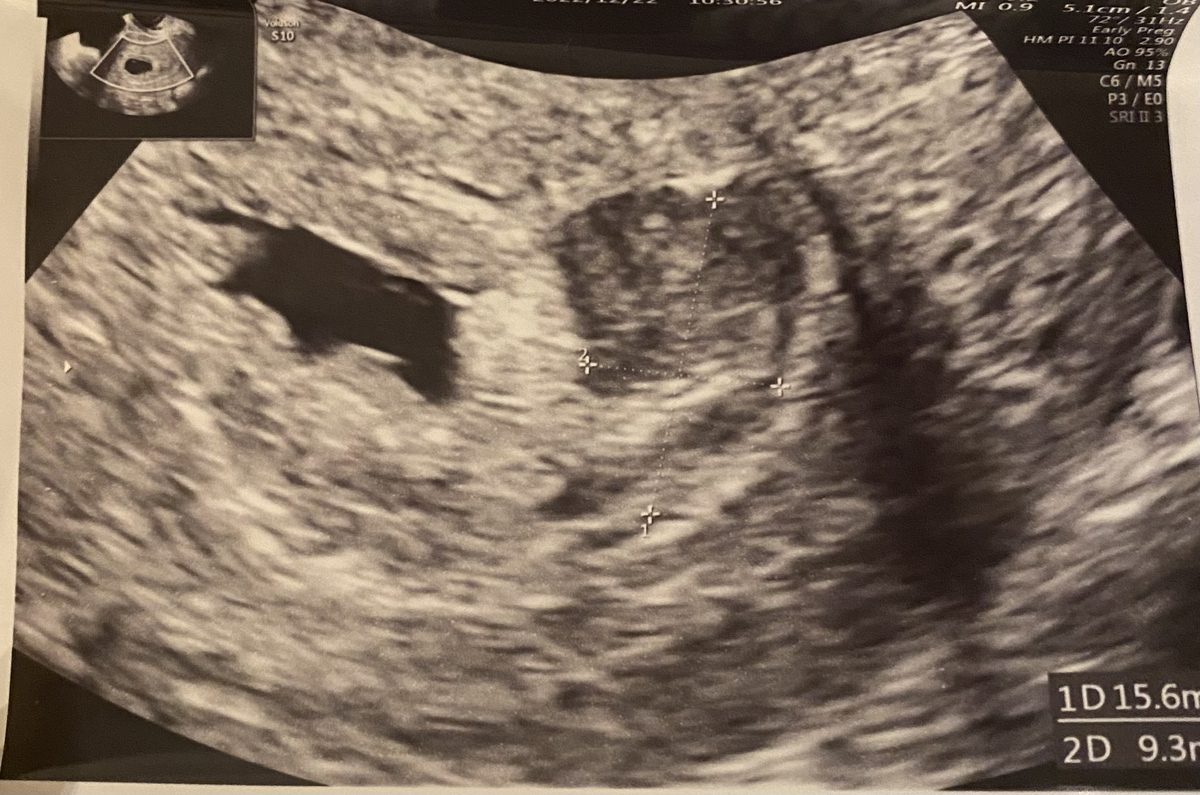

6w5dでしたが腹部エコーにて心拍確認もでき一安心。血腫はまだ残っていそうとのことなので年末年始は自宅安静もありゆっくり過ごしています。朝の空腹感による気持ち悪さ・寝る前の謎の寝苦しさとの戦いはありますが、気になる程の出血もなく経過できています。次の受診は年明けの1/3!どうかそこでも心拍確認ができますように。お腹ですくすく育っていることを信じて2022年を締めくくりたいと思います。

先日クリニックへBT18のタイミングで行ってきました。採血にてhcgのチェックと内診にて胎嚢の確認でした。

採血ではhcg14400と前回の陽性判定よりも上がっていて、内診では9.2mmの胎嚢が子宮内にあることを確認できました。診察室に呼ばれ結果採血も含め結果説明があったのですが、「9.2mmというのが胎嚢の大きさですか?」と質問した時に恐らく私の顔が少し不安げな様に映ったのか、先生から「そうですよ、何も問題ないサイズですから心配しなくて大丈夫ですよ」とおっしゃってくださいました。